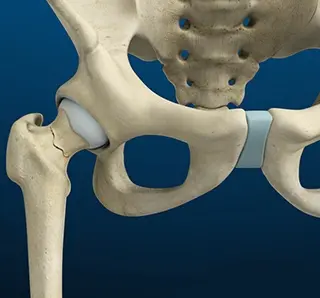

Stress Fractures of the Hip